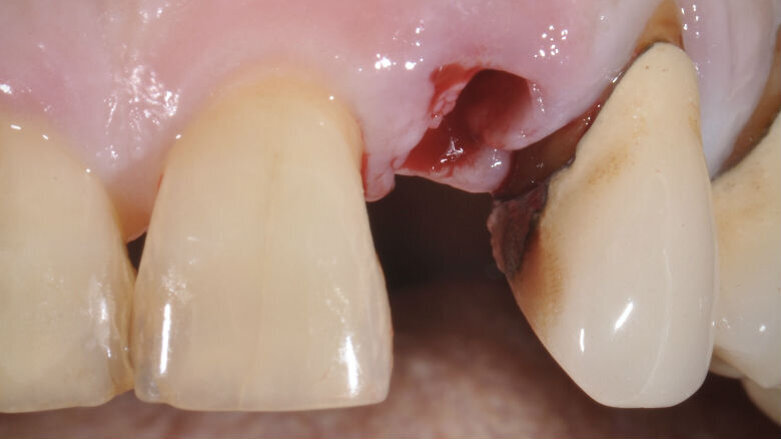

La paziente, B.G. di sesso femminile, di anni 71, è giunta alla nostra osservazione per la mobilità e lieve dolore a carico dell’elemento 2.2 (incisivo laterale superiore sinistro) (Fig. 1). All’esame ispettivo l’elemento presenta mobilità di grado 3. Al sondaggio parodontale presenta una tasca mesiale di 7 mm e di 3 mm lungo le altre superfici del dente. All’esame radiografico, eseguito con radiografia endorale periapicale, si osserva un’area di radiotrasparenza riconducibile a riassorbimento osseo soprattutto in sede mesiale (Fig. 2).

Il poter disporre di una tipologia di fixture estremamente orientata al conseguimento di elevati valori di stabilità primaria ha costituito un ulteriore elemento a favore di questa scelta. La paziente è stata sottoposta ad un trattamento preliminare a cielo coperto mediante levigatura radicolare. Il giorno dell’intervento, sotto profilassi antibiotica, è stata eseguita l’estrazione in maniera micro-traumatica e la rimozione mediante curettage dei tessuti infiammatori presenti. Non è stato eseguito un lembo di accesso, ma è stata verificata la presenza di tessuto osseo in sede vestibolare (Fig. 3).

Fig. 3_Alveolo post-estrattivo.